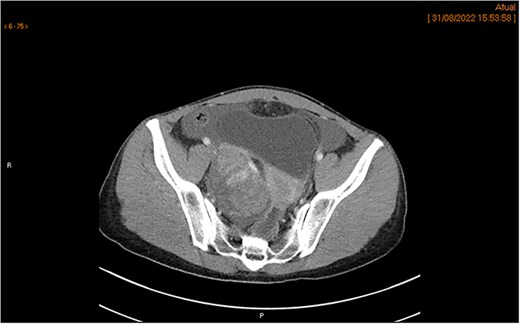

The MRI showed a heterogeneous right adnexal mass with mixed solid and cystic components. Moderate ascites was present in the subphrenic and paracolic gutters as well as the pelvic recesses. No suspicious lymphadenopathy or peritoneal thickening was observed on MRI (Fig. 1a and b). The subsequent CT scan confirmed a complex right ovarian lesion measuring approximately 80 × 67 × 57 mm, with solid contrast-enhancing components, highly suspicious for malignancy. Ascites and an indeterminate omental nodule were also noted. Additionally, subtle fat stranding in the omentum (in the lower portion of the greater omentum adjacent to the bladder), along with the moderate ascites, suggested early peritoneal carcinomatosis (Fig. 2).

CT scan demonstrates a right ovarian mixed lesion measuring 80 × 67 × 57 mm, with solid, contrast-enhancing components, ascites, and prevesical fat stranding nodule, with no other categoric signs of carcinomatosis.